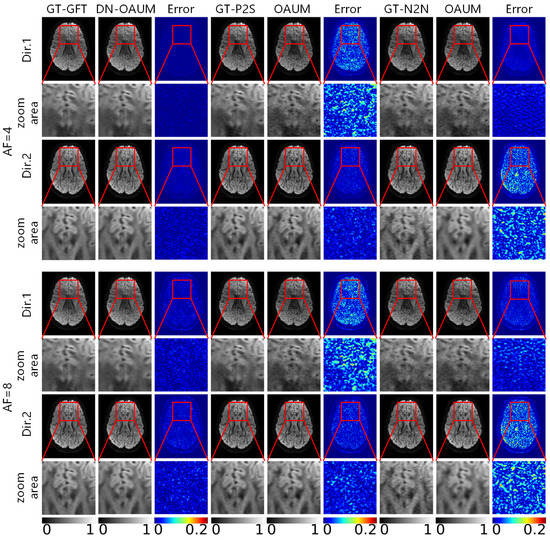

Figure 10 shows reconstructed DWIs using various methods with k-q space joint fast reconstruction on input noisy k-space undersampled data under 4-fold and 8-fold acceleration factors. The figure also includes their corresponding residual maps and zoomed-in maps. For the DN-OAUM method, the denoised result of original noisy DWIs obtained by GFT was used as the reference standard, i.e., the first column in the figure (GT-GFT). To preprocess denoised data for network training, Patch2Self and Neighbor2Neighbor methods were used for OAUM method. GT-P2S and GT-N2N represent data preprocessed using the Patch2Self and Neighbor2Neighbor methods for denoising, respectively, and their corresponding reconstructed DWIs after network training are shown on the right side. Similar to the above figures, two gradient directions’ results (Dir.1 and Dir.2) are displayed for each method to reflect both the k-space reconstruction effect and q-space reconstruction effect of networks. Observing the results in the Dir.1 gradient direction first shows that DN-OAUM reconstructed clear and smooth DWIs with very little visual difference from GT-GFT even when zoomed in significantly. However, OAUM trained using GT-P2S data preprocessing contained obvious noise points in its reconstructed DWIs; when observing zoomed-in regions compared to GT-P2S, they cover an additional layer of granular noise while image details became blurred due to the noise influence. Similarly, OAUM trained using GT-N2N also contained noise points in its reconstructed DWIs. Combining error maps revealed that DN-OAUM had minimal reconstruction errors among all methods in the Dir.1 direction with better image quality, while there were significant differences between the OAUM results using different denoising preprocessing techniques.

Figure 10. DWIs reconstructed by different methods using noisy data at different acceleration factors.

Upon examining the label data for each method in Figure 10, it is evident that GT-GFT and GT-P2S had fewer instances of visual noise compared to GT-N2N. Consequently, when training OAUM to reconstruct k-space with noisy data using GT-N2N, both the reconstructed result and label contained similar noise, resulting in relatively small errors. However, when using GT-P2S for training OAUM, there was no apparent noise in its label. Nevertheless, upon reconstructing k-space with data affected by noise, its reconstructed result contained a significant amount of noise, which differed significantly from that of GT-P2S. Therefore, this method performs exceptionally well on k-space reconstruction and can produce high-quality DWIs without significant visual noise compared to GT-GFT while minimizing error.

Upon observing the reconstructed DWIs in the gradient direction of Dir.2, the DN-OAUM method yielded clearly superior image quality. Although visually appealing, the OAUM method trained on GT-P2S data exhibited small particle-like noise when scrutinized under zoomed-in areas. Conversely, OAUM based on GT-N2N data produced blurry DWIs that lacked detail. Error maps corroborate these findings by demonstrating that DN-OAUM’s reconstruction results in the Dir.2 gradient direction were optimal. To better quantify image quality, we conducted a quantitative analysis comparison on reconstructed DWIs as presented in Table 6. The results indicate that the DN-OAUM method outperformed the other comparative methods in terms of quantitative indicators.

Table 6. RMSE, PSNR, and SSIM of DWIs reconstructed from different methods at different acceleration factors.

The results of visualizing DWIs reconstructed using various methods under an acceleration factor of 8 are also presented in Figure 10. In the gradient direction Dir.1, the DN-OAUM method showed clear details in the DWIs, while the OAUM method was severely affected by noise. Similarly, for an acceleration factor of 8 in the Dir.2 gradient direction, the DN-OAUM method produced better image quality than the OAUM method. Table 6 provides quantitative results that show a decrease in the RMSE and an improvement in the PSNR and SSIM with the DN-OAUM method compared to the OAUM method.